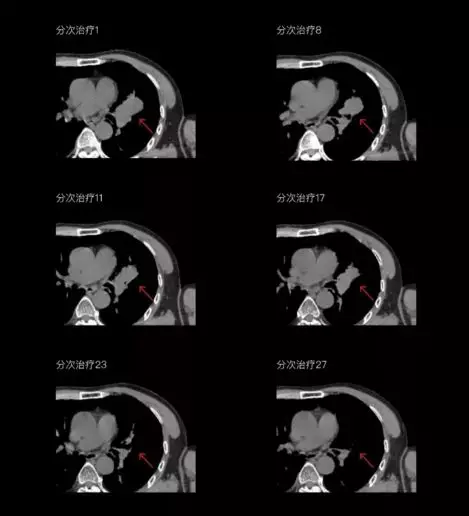

一體化CT-linac讓自適應(yīng)放療ART概念變?yōu)楝F(xiàn)實(shí)。患者全療程狀態(tài)監(jiān)控,適時(shí)在線調(diào)整治療計(jì)劃,精準(zhǔn)控制治療劑量,為患者動(dòng)態(tài)定制個(gè)體化治療方案。uAI賦能智能勾畫(huà)和自動(dòng)計(jì)劃,秒級(jí)勾勒靶區(qū)和危及器官,大幅縮短自適應(yīng)放療時(shí)間。

聯(lián)影CT-linac全程監(jiān)測(cè)治療過(guò)程病灶的變化,及時(shí)調(diào)整和優(yōu)化治療方案